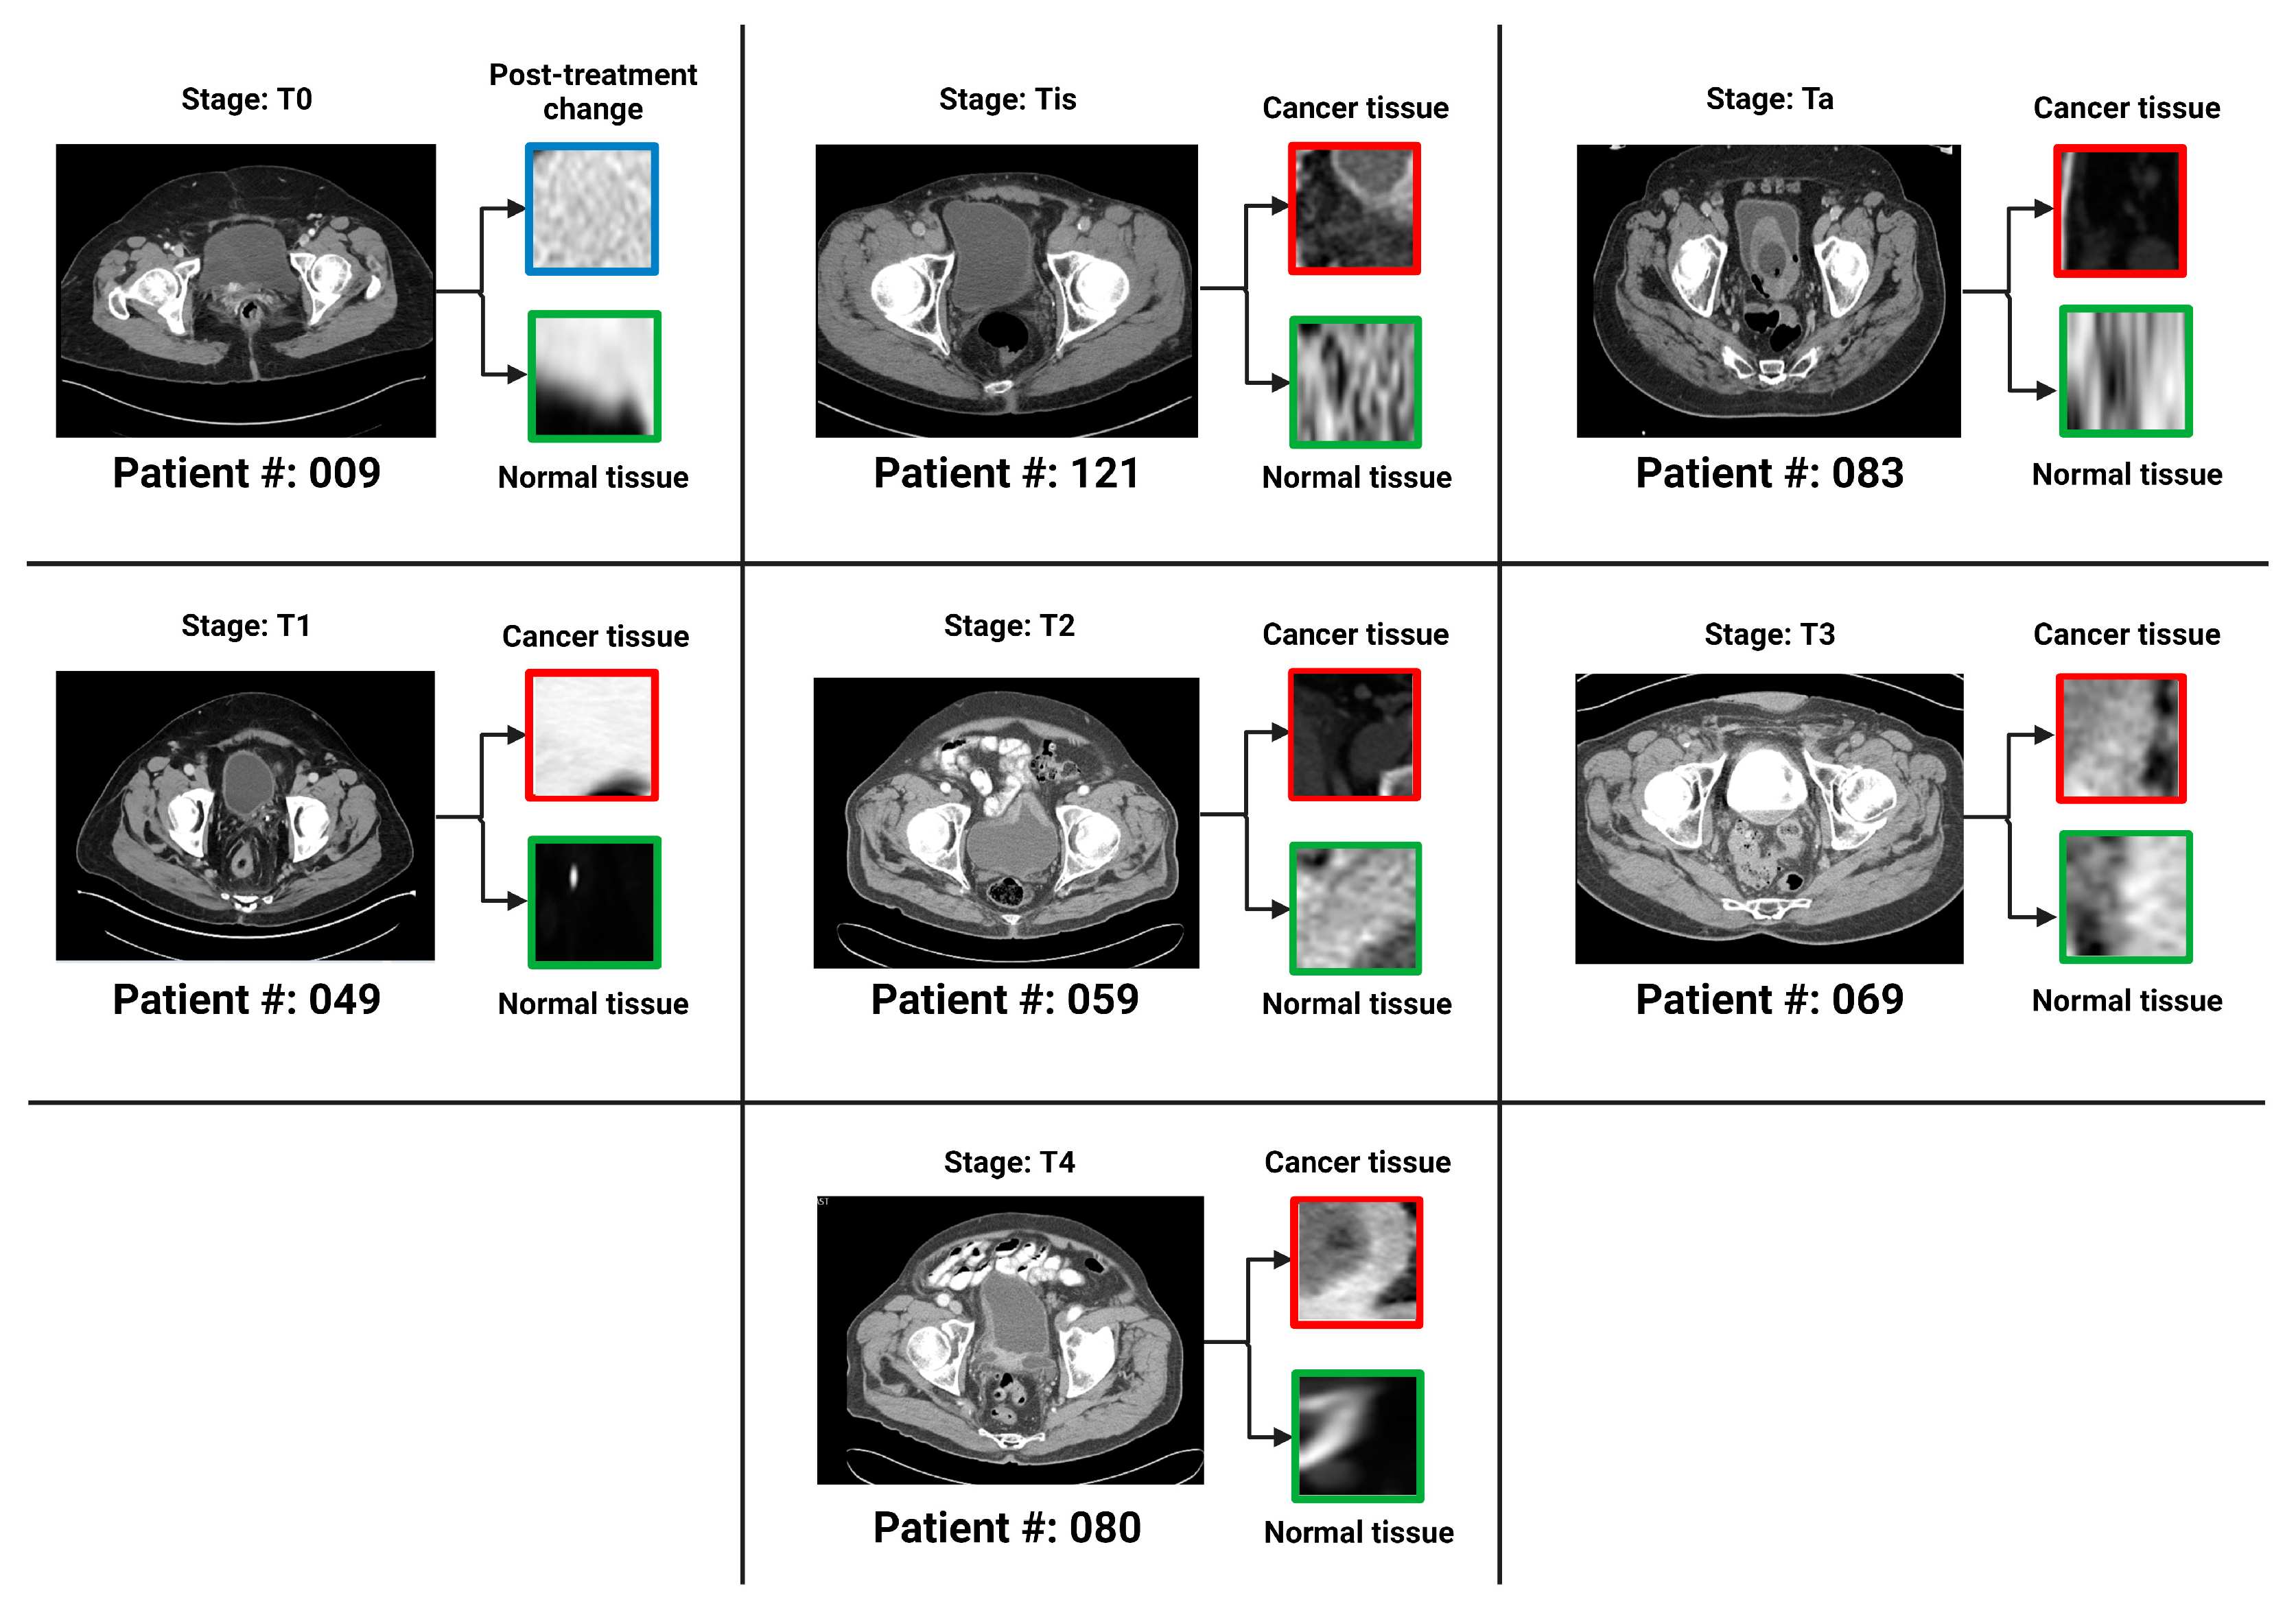

- Sarkar, S.; Min, K.; Ikram, W.; Tatton, R.W.; Riaz, I.B.; Silva, A.C.; Bryce, A.H.; Moore, C.; Ho, T.H.; Sonpavde, G.; et al. Performing Automatic Identification and Staging of Urothelial Carcinoma in Bladder Cancer Patients Using a Hybrid Deep-Machine Learning Approach. Cancers 2023, 15, 1673. [Google Scholar] [CrossRef]

- Li, J.; Qiu, Z.; Cao, K.; Deng, L.; Zhang, W.; Xie, C.; Yang, S.; Yue, P.; Zhong, J.; Lyu, J.; et al. Predicting muscle invasion in bladder cancer based on MRI: A comparison of radiomics, and single-task and multi-task deep learning. Comput. Methods Programs Biomed. 2023, 233, 107466. [Google Scholar] [CrossRef]

- Song, H.; Yang, S.; Yu, B.; Li, N.; Huang, Y.; Sun, R.; Wang, B.; Nie, P.; Hou, F.; Huang, C.; et al. CT-based deep learning radiomics nomogram for the prediction of pathological grade in bladder cancer: A multicenter study. Cancer Imaging 2023, 23, 89. [Google Scholar] [CrossRef] [PubMed]

- Zhang, G.; Xu, L.; Zhao, L.; Mao, L.; Li, X.; Jin, Z.; Sun, H. CT-based radiomics to predict the pathological grade of bladder cancer. Eur. Radiol. 2020, 30, 6749–6756. [Google Scholar] [CrossRef] [PubMed]

- Zhang, G.; Wu, Z.; Zhang, X.; Xu, L.; Mao, L.; Li, X.; Xiao, Y.; Ji, Z.; Sun, H.; Jin, Z. CT-based radiomics to predict muscle invasion in bladder cancer. Eur. Radiol. 2022, 32, 3260–3268. [Google Scholar] [CrossRef] [PubMed]